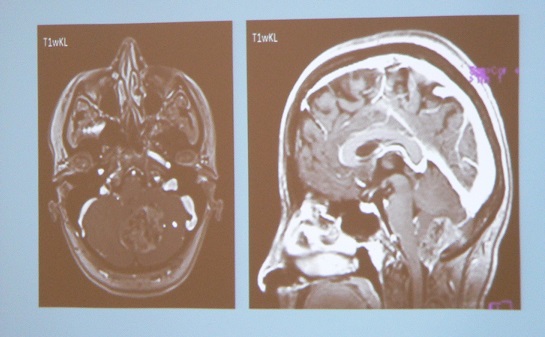

Neurochirurgiou v oblasti mozgových nádorov hýbe neuromonitoring. Skonštatovali to účastníci siedmeho ročníka Žilinských neurochirurgických dní, ktorý sa dnes skončil v Terchovej. „Čo sa týka mozgových nádorov dnes tá diagnostická technika postúpila, ale aj počas operácie veľmi vpred natoľko, že my dokážeme nielen zistiť, kde sú ktoré štruktúry mozgu uložené, ale dokážeme si to aj na snímkach overiť počas operácie a dokážeme sledovať aj ich funkciu. Celkovo by sa to dalo nazvať, že to je neuromonitoring," uviedol neurochirurg profesor Juraj Šteňo.

Výmena odborných skúseností a poznatkov v liečbe mozgových ochorení a ochorení chrbtice, je cieľom siedmeho ročníka Žilinských neurochirurgických dní. Trojdňový kongres sa dnes začal v Terchovej. „Tento rok máme hlavnú nosnú tému mozgové nádory, pričom dnes popoludní začína panelová diskusia o zhubných mozgových nádoroch. Zajtra budeme pokračovať v prednáškach o zhubných i nezhubných mozgových nádoroch, operačných technikách a možnostiach spôsobu liečby. V piatok nás čakajú témy týkajúce sa ochorenia chrbtice a operácie s tým súvisiace," priblížil primár žilinského neurochirurgického oddelenia Peter Bačinský.